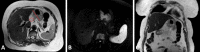

Accurate preoperative staging of gastric cancer and the assessment of tumor response to neoadjuvant treatment is of importance for treatment and prognosis. Current imaging techniques, mainly endoscopic ultrasonography (EUS), computed tomography (CT) and 18F-fluorodeoxyglucose positron emission tomography (18F-FDG PET), have their limitations. Historically, the role of magnetic resonance imaging (MRI) in gastric cancer has been limited, but with the continuous technical improvements, MRI has become a more potent imaging technique for gastrointestinal malignancies. The accuracy of MRI for T- and N-staging of gastric cancer is similar to EUS and CT, making MRI a suitable alternative to other imaging strategies. There is limited evidence on the performance of MRI for M-staging of gastric cancer specifically, but MRI is widely used for diagnosing liver metastases and shows potential for diagnosing peritoneal seeding. Recent pilot studies showed that treatment response assessment as well as detection of lymph node metastases and systemic disease might benefit from functional MRI (e.g. diffusion weighted imaging and dynamic contrast enhancement). Regarding treatment guidance, additional value of MRI might be expected from its role in better defining clinical target volumes and setup verification with MR-guided radiation treatment.